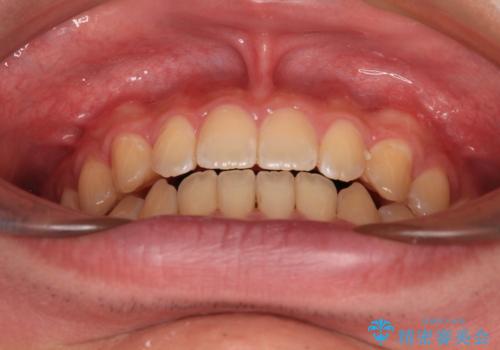

- 上下前歯の隙間を気にして来院された患者様です。

飲み込みや話をするときに舌を突出させる癖が強くあり、それが原因でスペースが空いていました。

舌癖を改善するためのトレーニングを行いながら、ワイヤー装置を用いて前歯の隙間を閉じていくこととしました。